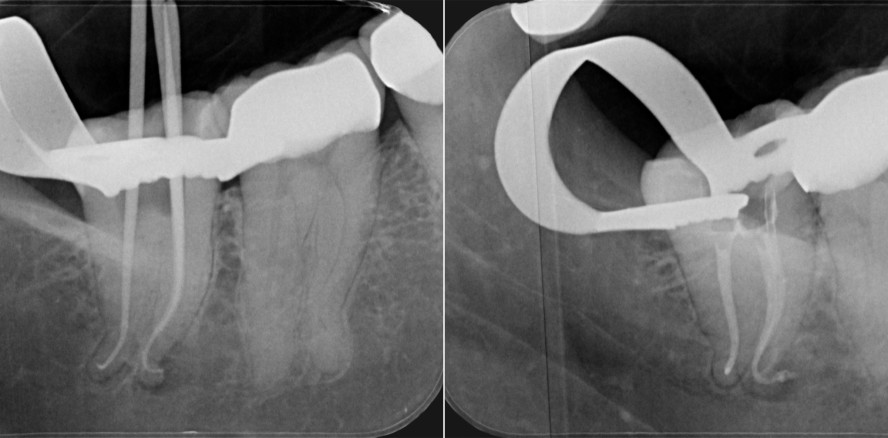

Beim Anblick des Abschlussröntgenbildes dürfte sich Dr. David William Christofzik aus Kiel wohl erleichtert und zufrieden gefühlt haben. Wie kam es zu diesem – ja, Aufbereitungs-Kunstwerk, und welche Ausstattung half ihm dabei? Im Interview verrät der Behandler das Prozedere eines komplexen Patientenfalls.

Die 40-jährige Patientin wurde mir von einem Überweiser geschickt, der die Behandlung an Zahn 47 bereits begonnen hatte. Er hatte korrekt trepaniert und auch alle Kanäle mesiobukkal, mesiolingual und distal aufgefunden, jedoch es nicht geschafft, deren unteres, stark gekrümmtes Drittel aufzubereiten. Er hat den Wurzelkanal nicht verblockt, sondern hat an der richtigen Stelle aufgehört zu behandeln und überwiesen. Die Patientin stand einen Tag später in meiner Praxis und klagte über hochakute Schmerzen, verursacht durch das entzündete Nervengewebe im apikalen Drittel.

Es brauchte für diese Indikation definitiv wärme­behandelte Feilen wie FQ (Komet Dental), die mir die nötige Flexibilität bieten. Denn theoretisch soll die Flexibilität dieser Instrumente gerade im Grenz­bereich bei starken Krümmungsradien zu deutlichen Aufbereitungsvorteilen führen. Ob ich das praktisch in diesem Extremfall würde umsetzen können, wusste ich zu diesem Zeitpunkt noch nicht. Glücklicherweise gibt es überhaupt solche Weiterentwicklungen der Nickel-Titan-Produkte. Meine Entscheidung fiel außerdem auf das FQ-System, weil es Feilendurchmesser ISO 20-55 und Taper .04/.06 bietet, mit denen sich grundsätzlich ein Behandlungsspektrum von einfach bis komplex abdecken lässt. Und ich wusste, dass ich mit dem EndoPilot in mehrfacher Hinsicht eine sichere Komplettlösung an meiner Seite habe: als Apexlokator in Echtzeit mit Stoppfunktion, zur Aufbereitung und zur dreidimensionalen Obturation. Das alles war also einen Versuch wert, sich an einen Grenzfall zu wagen, der herausfordernd war und nicht alle Tage vorkommt.

Nach der Gleitpfaderstellung startete ich mit FQ (020/.04). Bereits hier wären normale, nicht vorbiegbare NiTi-Feilen ans Limit gekommen. Die neuralgische Grenze bei wärmebehandelten/nicht wärmebehandelten Feilen liegt für mein Empfinden exakt zwischen den Größen 015 und 020. Ich arbeitete mich also immer ein paar Schritte weiter im Kanal vorwärts, von FQ (020/.04) zu FQ (020/.06). Das reichte mir aber noch nicht als Endaufbereitungsgröße und ich sprang auf FQ (025/.06). Zwischendurch spülte ich ausgiebig und rekapitulierte jeweils mit der Patency Handfeile. An dieser Stelle möchte ich herausstellen, dass dieser Fall schön aufzeigt, dass man sich nicht immer zwingend an ein starres Aufbereitungsprotokoll halten muss. Die Kombination beider Aufbereitungswege zeichnet das FQ-System besonders aus und kann übrigens auch für einfachere Fälle angewendet werden.

Ja, absolut. Die Anatomie des Kanalsystems bestimmt die Art der Obturationsmethode. Mir war von Anfang an klar, dass dieser Fall nicht per DownPack- und BackFill-Methode mittels der warm-vertikalen Kondensationstechnik zu lösen war. Der Grund: Die Krümmungen im apikalen Drittel waren in diesem Grenzfall ja mehrere Milli­meter lang und somit wäre eine Warm-vertikal-Kondensation kaum möglich gewesen. Aufbereitungsgröße und Taper waren dafür aber viel zu gering. Ich sah die Lösung in der hydraulischen, biokeramischen Wurzelfüllung mit KometBioSeal (Komet Dental).

Ich brachte mit der grazilen Spritze KometBioSeal zu zwei Dritteln in das Kanalsystem ein und erzeugte dann mit einem passenden Masterpoint den hydraulischen Druck für die Verteilung in die Spitze. Wichtig ist außerdem, die Guttapercha nach Abschmelzen koronal gut mit Pluggern zu verdichten, um den perfekten Verschluss des Kanalsystems zu erreichen. Die Abtrennung der Guttapercha klappt übrigens sauber mit der Heizspitze vom DownPack (eine mögliche Erweiterung des EndoPilot), das ist eine viel einfachere Technik als mit einem über der Flamme erhitzten Instrument.